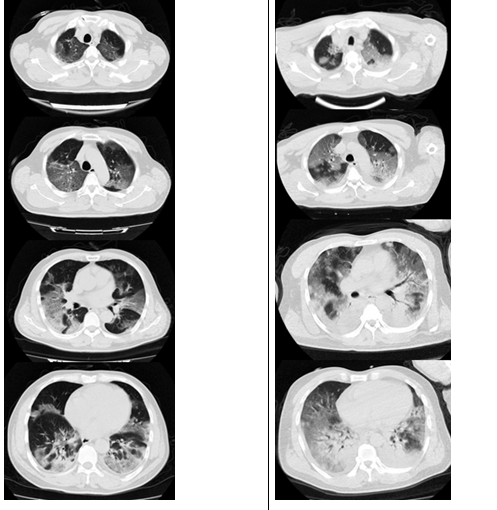

IAA的影像学特征具有提示意义,其影像学一般是在磨玻璃影背景上新发的结节和斑片影,病变特点是沿着支气管血管束分布,而典型的空洞和新月征不多见。

图片

大片实变影也相对特异,且提示预后差!